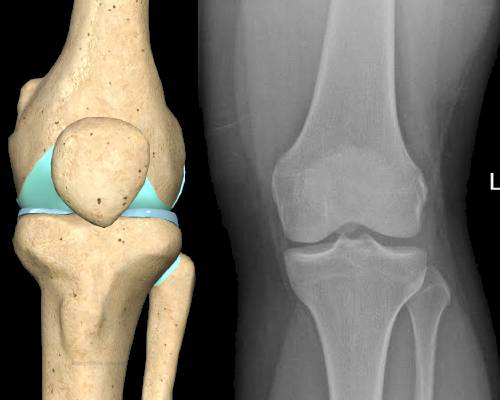

Radiographs are 2 dimensional representations of often complex 3-dimensional structures. The reporter/reader must then convert these 2-dimensional appearances back into a 3-dimensional mental picture. Clearly, there are many opportunities to make errors along the way, for example when attempting to describe relative positions of fracture fragments, position/appearances of a bony lesion and so on.